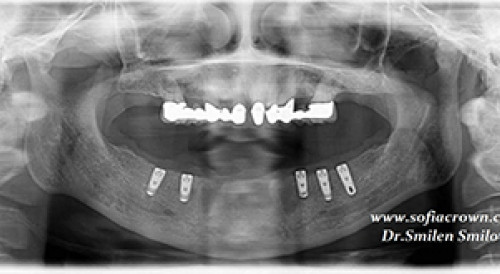

Поставени са пет импланта в долна челюст. Предстоящо имплантиране на още два, в областта на екстрахираните кучешки зъби. Поставени са пет импланта в долна челюст. Предстоящо имплантиране на още два, в областта на екстрахираните кучешки зъби.